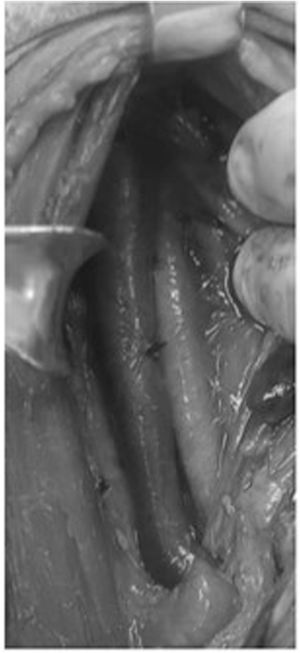

ResultsA total of 70 neck exploration (Fig. 2) cases were reviewed with a mean age was 33 (± 10.4) years. 66 (94%) male and 4 females (6%) were included in the study. Mean hospitalization time was 5 days, with only 6 (9%) patients staying more than 2 weeks. 40 (57%) patients were injured by GSW and 30 (43%) by SW. All patients had a Glasgow Coma Score of 15 upon arrival to the emergency room (ER). Extra-cervical injuries were observed in 12 (17%) patients.